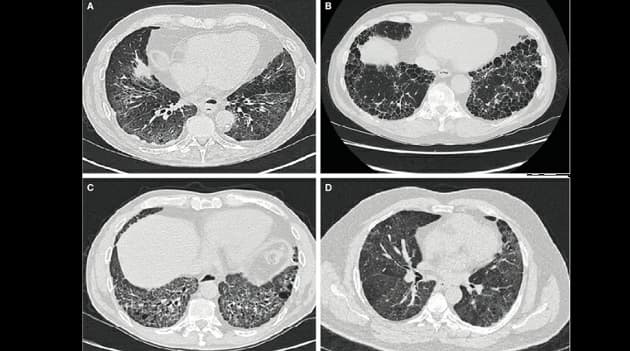

Interstitielle lungesygdomme er en heterogen gruppe af sjældne sygdomme med mere end 150 undertyper med idiopatisk pulmonal fibrose som den hyppigste tilstand. Statusartiklen af Sritharan et al fokuserer på andre subtyper, som dog har flere fællestræk med den idiopatiske lungefibrose, herunder progredierende fibrosedannelse og dårlig prognose. Forfatterne konkluderer, at antifibrotisk behandling, som nintedanib og pirfenidon, også ser ud til at have effekt ved disse subtyper af intersitiel lungesygdom.

Behandling af progressiv fibrotisk interstitiel lungesygdom

Sajitha Sophia Sritharan, Line Kølner-Augustson, Sissel Kronborg-White et al